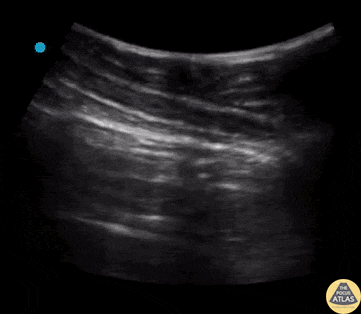

Kritik hastada akciğer ultrasonunda en önemli değerlendirme başlığı pnömotoraks varlığıdır. Hasta çoğunlukla supin pozisyonda olduğundan, hava en az bağımlı (en üstte kalan) bölgede birikir. Bu nedenle görüntüleme genellikle:

yapılır.

Yüksek frekanslı prob kullanılmalı ve sagittal planda değerlendirme yapılmalıdır. Her iki hemitoraks mutlaka karşılaştırmalı olarak incelenmelidir.

Değerlendirmede temel bulgular:

Bu bulgulardan herhangi birinin varlığı, pariyetal ve viseral plevranın temas halinde olduğunu gösterir; yani pnömotoraks yoktur.

Lung sliding, kaburgaların hemen derininde görülen hiperekojen plevral hat boyunca oluşan “ışıltılı / titreşimli” hareket şeklinde izlenir. Kaburgalar plevral hattı tanımlamak için referans olarak kullanılmalıdır.